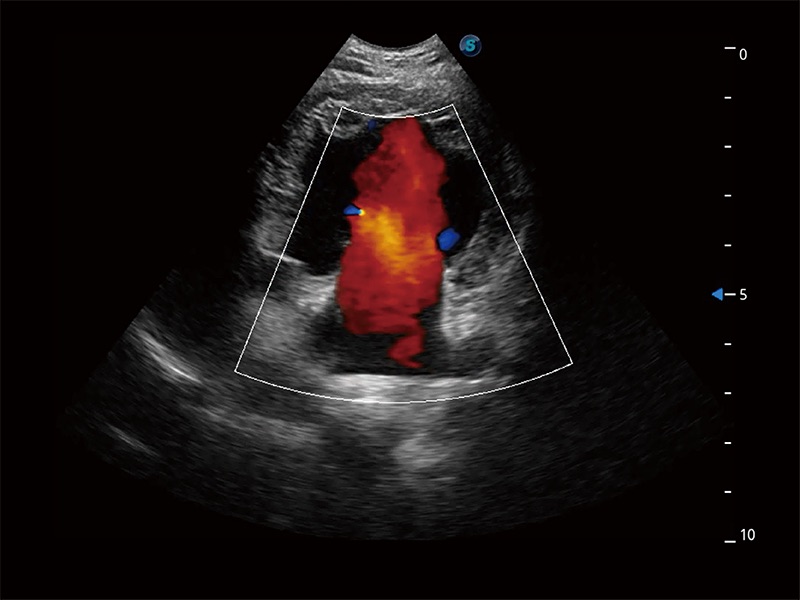

(犬)胎儿主动脉弓立体血流

• Bright Flow 立体血流成像

在传统二维血流成像的基础上,呈现血流的立体感,具有动感的生命力之美。即便是微小的血管也能轻松应对,提高了血流的视觉敏感性。

优异的基础图像

ProPet 80 全新的动物超声智能软件和丰富的探头群,为动物医生提供了高清晰度和精细分辨率的图像,无论在宠物、马科、畜牧还是实验室动物等应用中都可以轻松应对,为您的日常工作带来满意的体验。